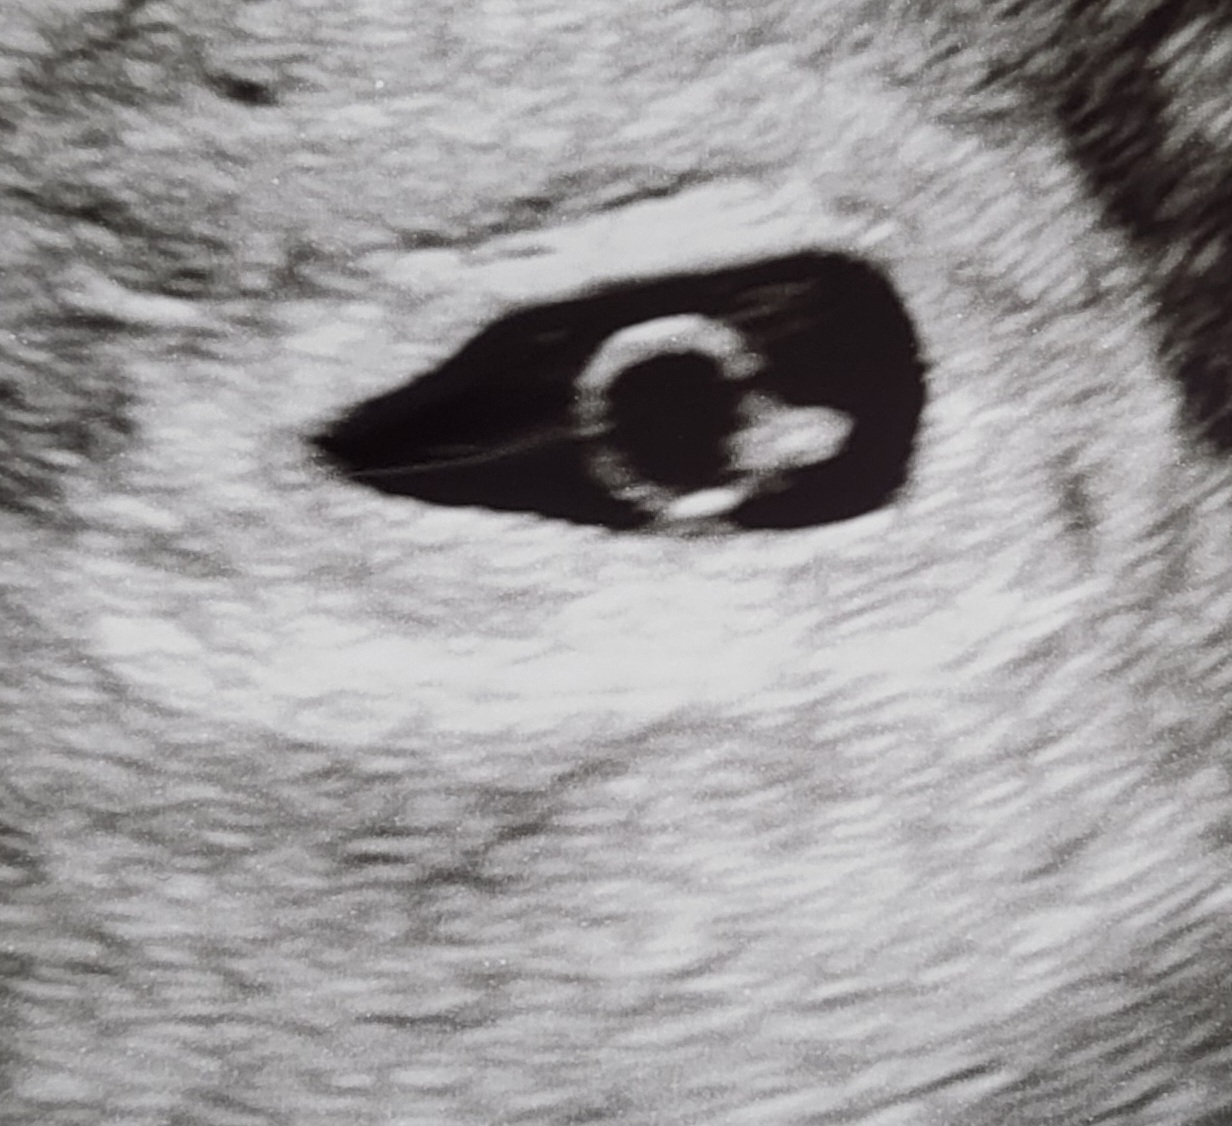

| 가슴 떨리는 임신 이야기를 공유해 주세요. | 저에게 임신은 한순간에 찾아온 기적이 아니라, 긴 기다림 끝에 다가온 선물이었습니다. 수없이 반복된 실패와 좌절 속에서 불안이 마음을 짓눌렀지만, 그럼에도 작은 희망 하나를 붙잡고 계속 걸어왔습니다. 그러던 어느 날, 초음파 화면과 함께 들려온 아기의 심장 박동 소리. 세상의 모든 소리가 멈춘 듯했고, 제 가슴은 떨림과 눈물로 가득 찼습니다. 몇 년간의 고생과 눈물이 단번에 보상받는 것 같은 벅찬 감동이었습니다. |

| 치료 도중 느꼈던 가장 기뻤던 순간과 절망적인 것들은 무엇인가요? 잊지 못할 경험이 있나요? | 오랜 기간 시험관 시술을 반복했지만 번번이 배아 착상이 되지 않아, 피검사 날마다 너무 힘들고 눈물이 날 때가 많았습니다. 매번 기대했다가 다시 무너지는 과정이 반복되니 몸도 마음도 지쳐갔습니다. 그런데 결국 서울IVF여성의원에서 임신에 성공하게 되었고, 아기의 심장 박동 소리를 처음 들었을 때는 그동안의 모든 고생이 단번에 씻겨 내려가는 듯했습니다. 기쁨과 감사함이 벅차올라 지금도 그 순간을 잊지 못합니다. |